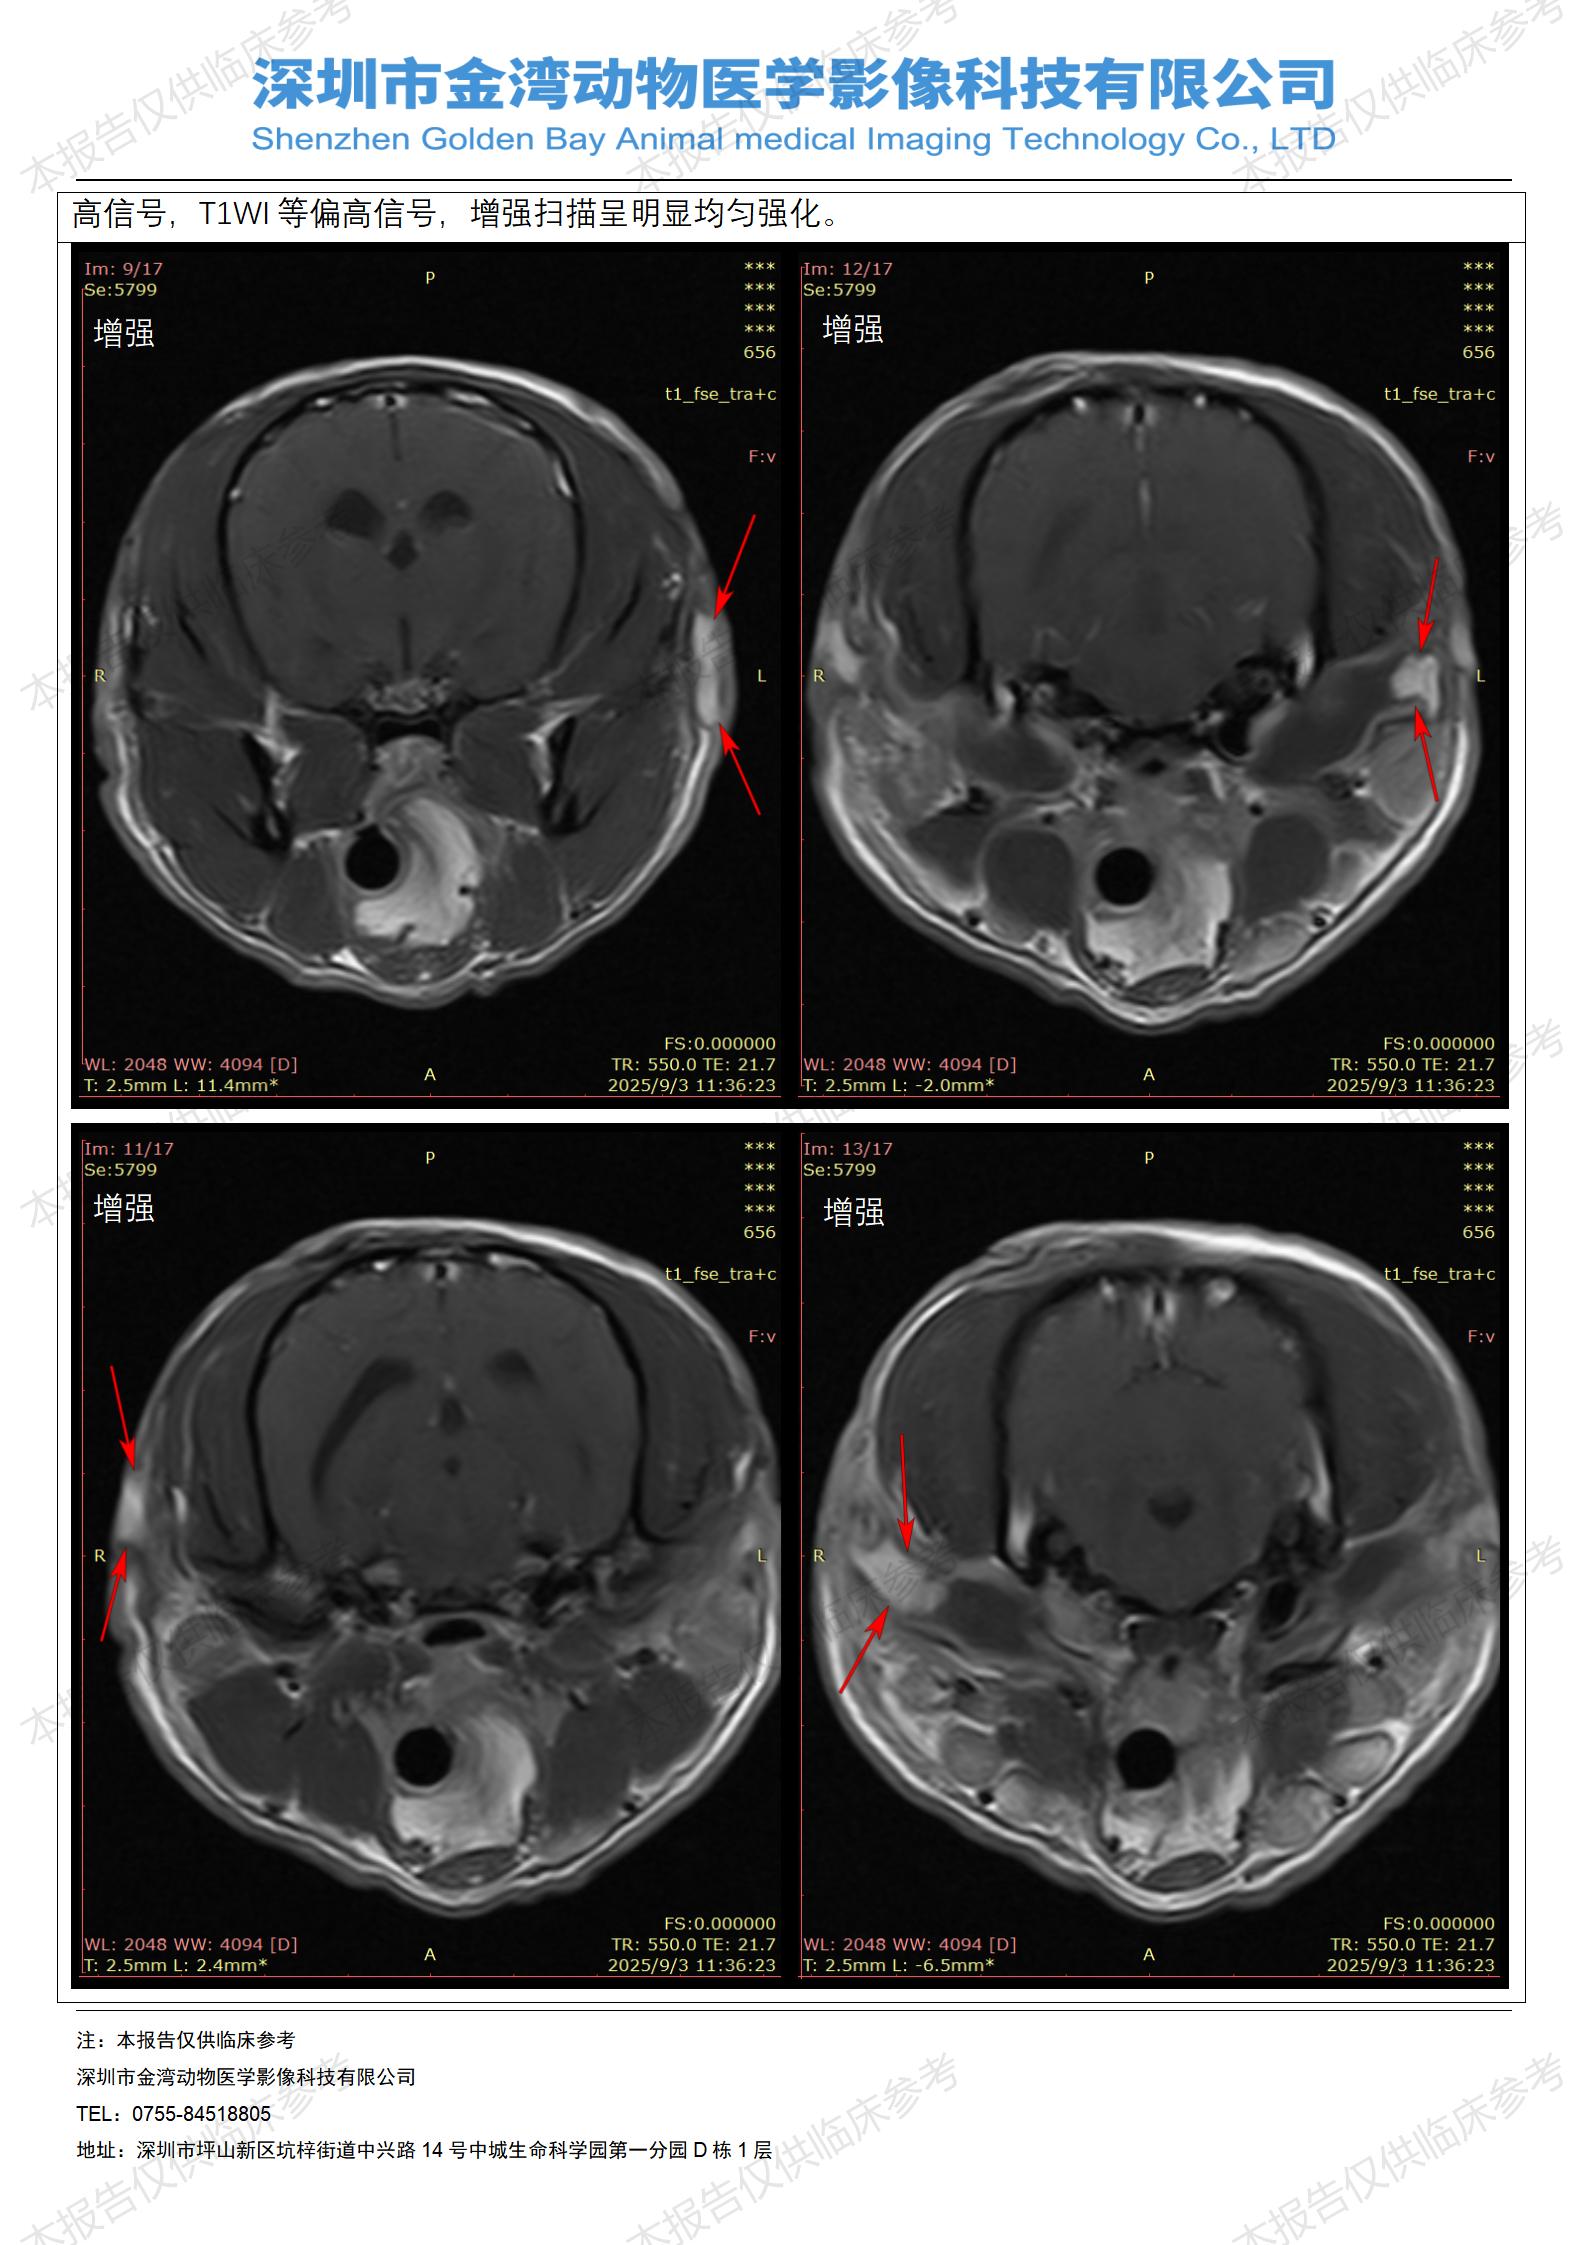

金石医疗MRI影像诊断案例:一例狗双耳流脓的诊断报告